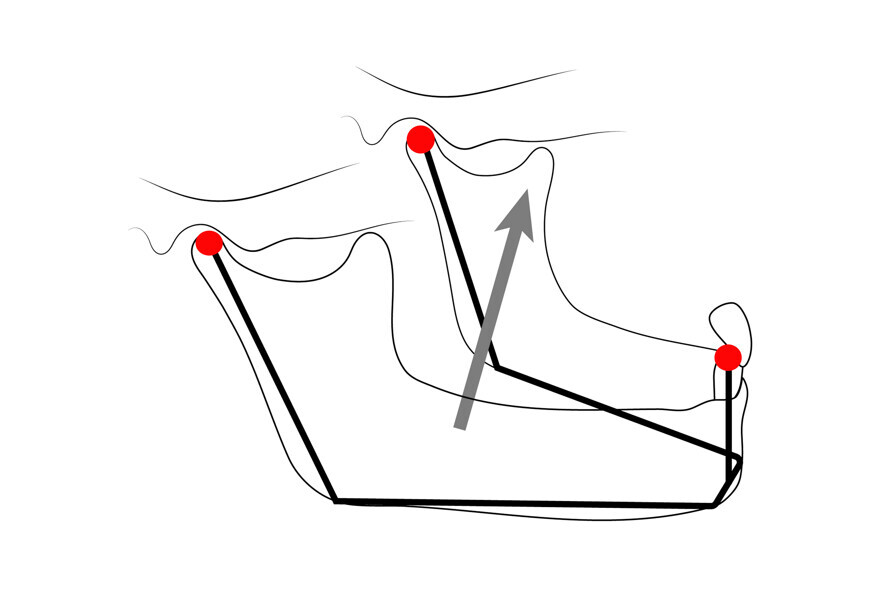

Fig. 9: The condyle position is based on the vector of force of the elevator muscles—perpendicular to the contour of the eminence.